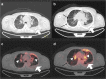

Methods: During the period of maximum incidence of the global pandemic in one of the most affected regions of Spain, there were 145 patients that met inclusion and exclusion criteria and were included in the study. Imaging findings previously described such as ground-glass opacities with low [18F]-FDG uptake were considered images suspicious for SARS-CoV-2 infection. Patients with these findings were referred to RT-PCR testing and close follow-up to confirm the presence or absence of COVID-19.

Results: Suspicious lung imaging findings were present in 7 of 145 patients (4.8%). Five of these 7 patients were confirmed as presenting SARS-CoV-2 infection, this is, COVID-19. In the remaining two, it was not possible to confirm the presence of COVID-19 with RT-PCR, although in one of them, PET/CT allowed an early diagnosis of a lung infection related to a bacterial pneumonic infection that was promptly and adequately treated with antibiotics.